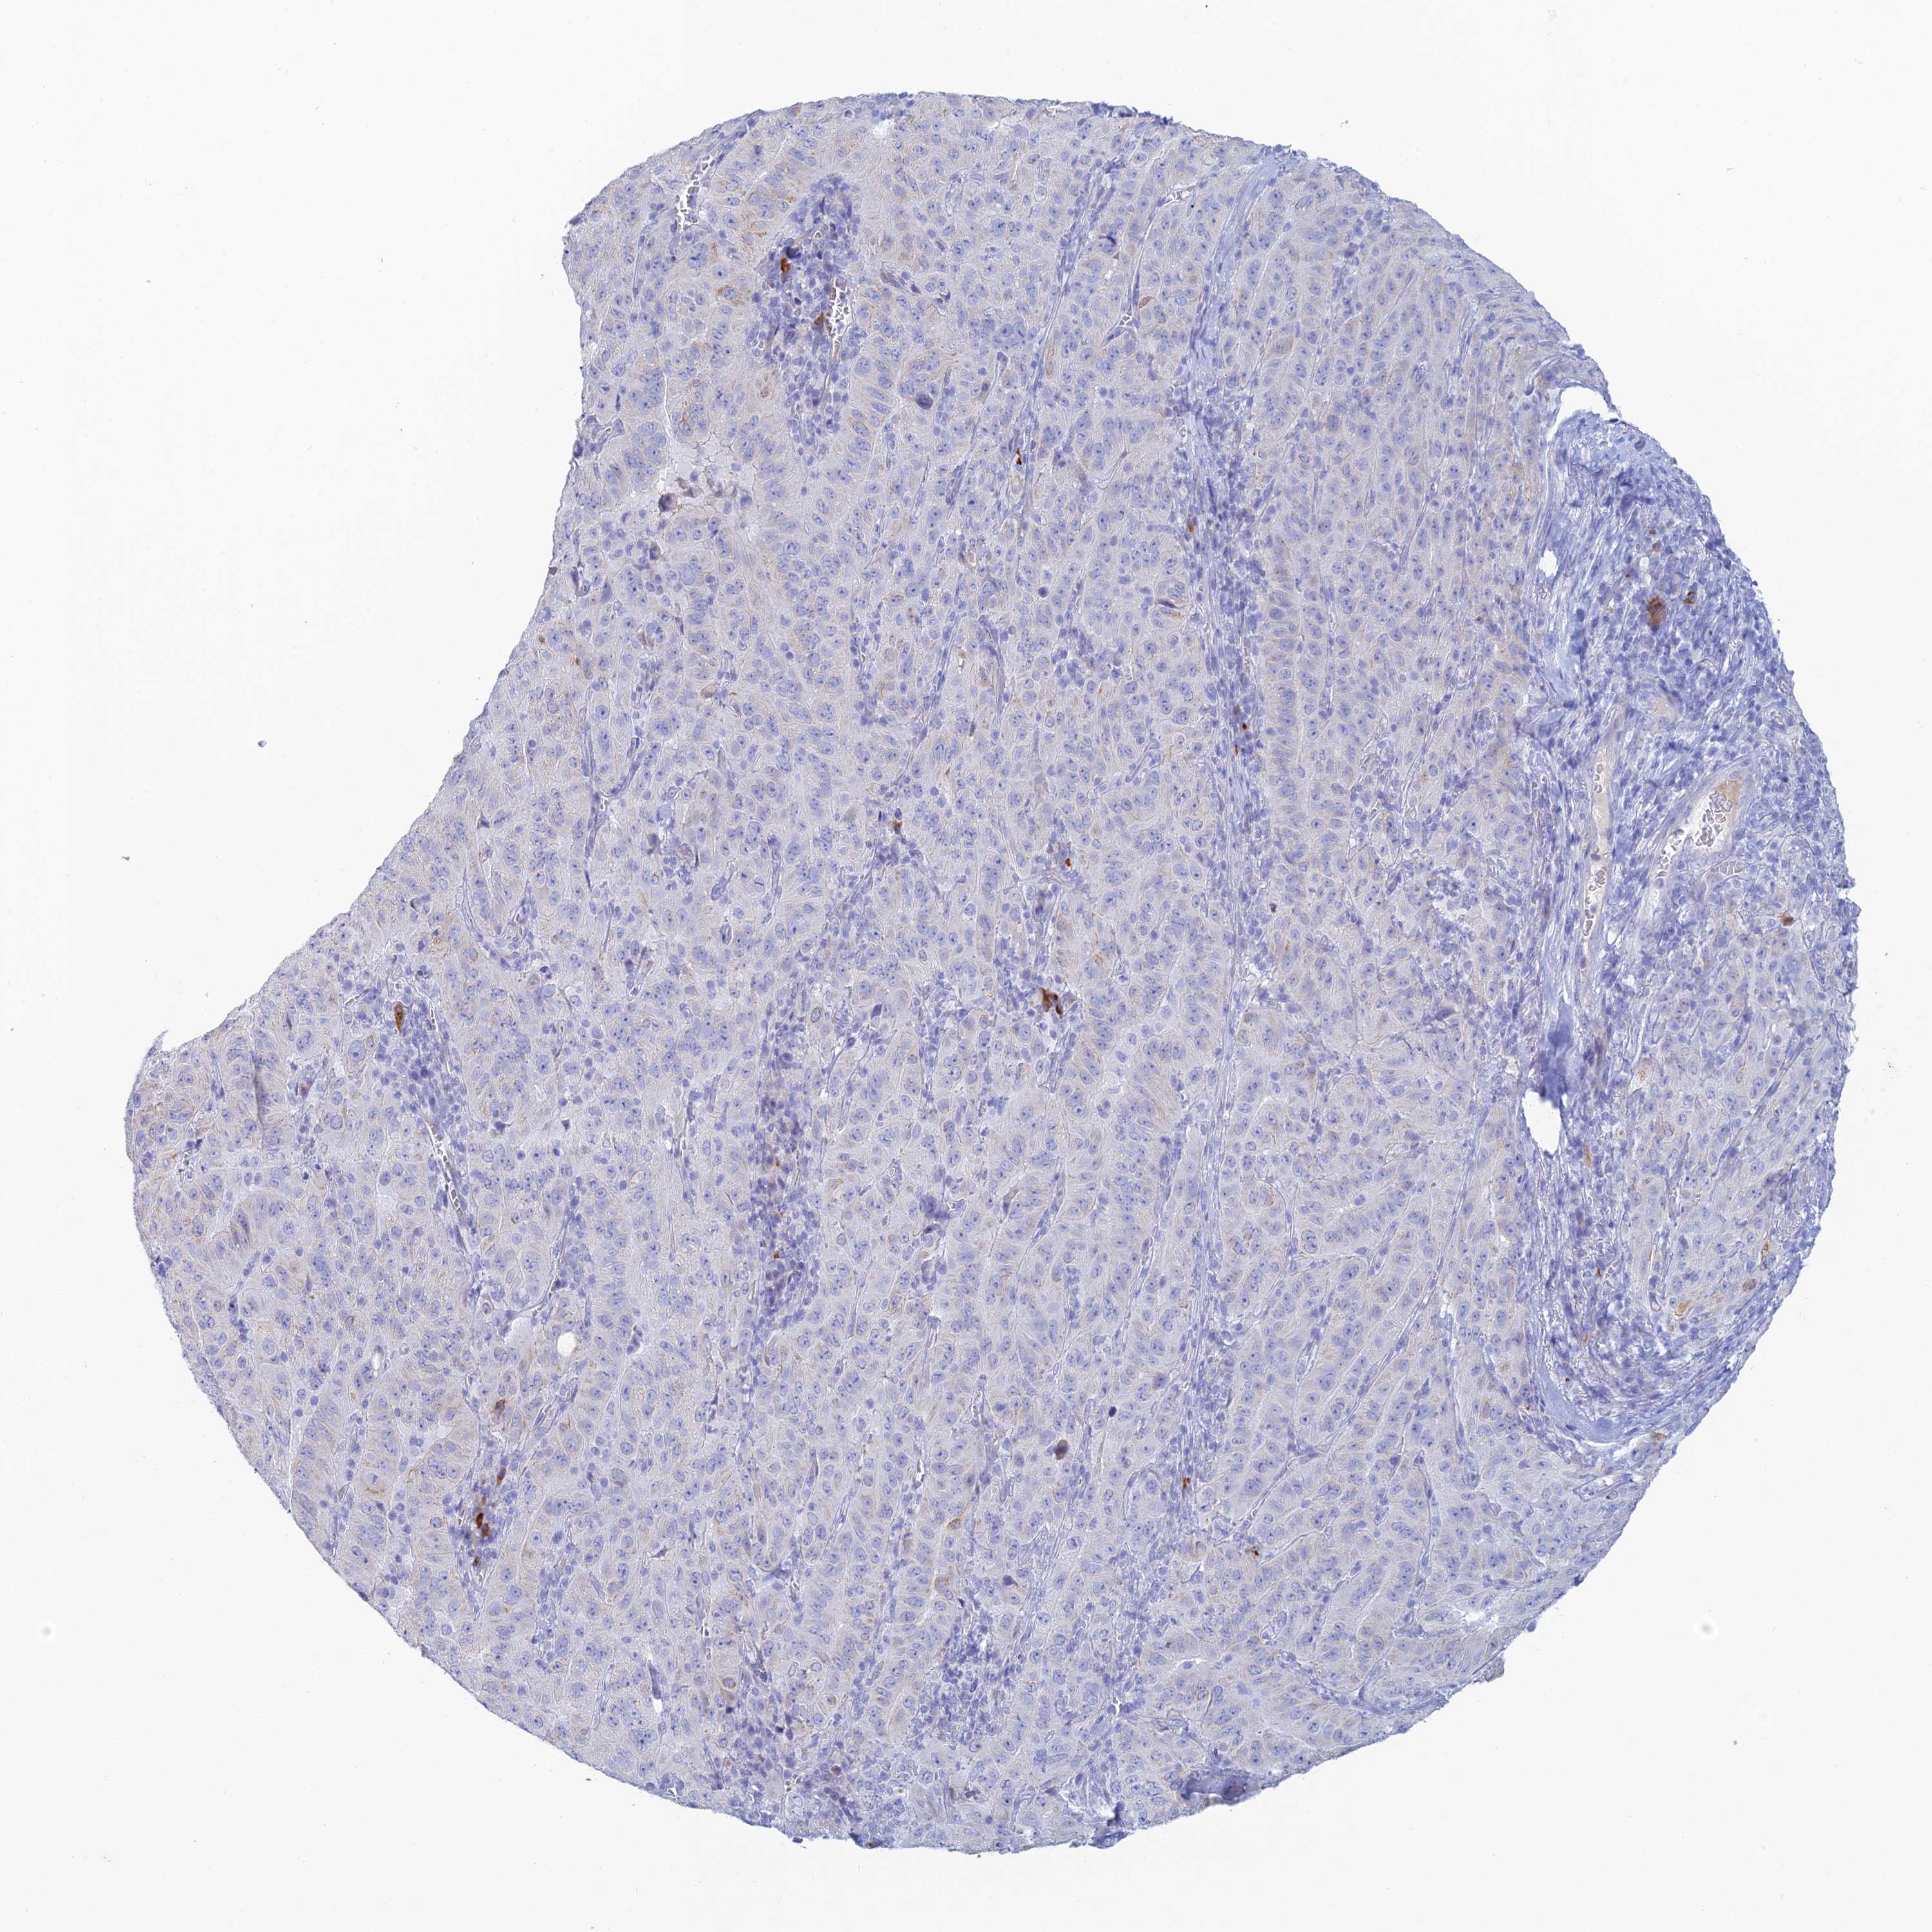

PANCREATIC CANCER - Protein expressioni

A mouse-over function shows sample information and annotation data. Click on an image to view it in a full screen mode. Samples can be filtered based on level of antibody staining by selecting one or several of the following categories: high, medium, low and not detected. The assay and annotation is described here.

Note that samples used for immunohistochemistry by the Human Protein Atlas do not correspond to samples in the TCGA dataset.

Antibody stainingi

Antibody staining in the annotated cell types in the current human tissue is reported as not detected, low, medium, or high, based on conventional immunohistochemistry profiling in selected tissues. This score is based on the combination of the staining intensity and fraction of stained cells.

Each image is clickable and will lead to virtual microscopy that enables deeper exploration of all samples and also displays staining intensity scores, fraction scores and subcellular localization as well as patient and tissue information for each sample.

Antibody HPA039408

Staining

High

Medium

Low

Not detected

Intensity

Strong

Moderate

Weak

Negative

Quantity

>75%

75%-25%

<25%

None

Location

Nuclear

Cytoplasmic/membranous

Cytoplasmic/membranous,nuclear

Adenocarcinoma, NOS